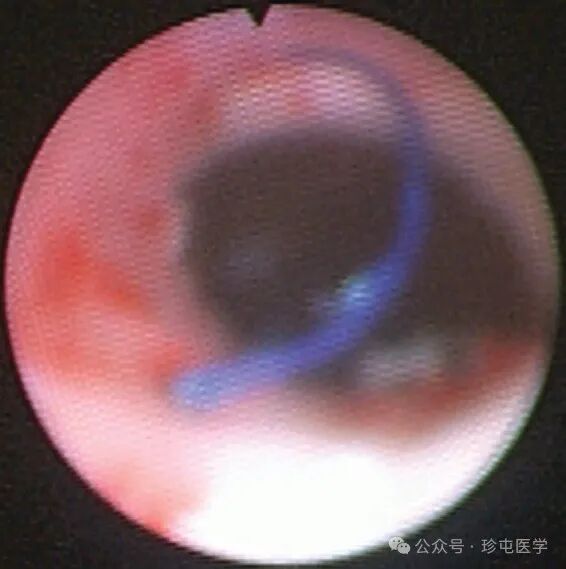

70F 有复发性 L UPJo 病史,s/p 之前接受过机器人 L 肾盂成形术,然后进行肾盂切开术 x2

腹部 CT 无造影显示手术夹靠近输尿管肾盂连接处 (UPJ)。从此图像很难判断手术夹是否正在侵蚀输尿管。

在手术中使用异物的一个并发症是可能侵蚀附近的组织。内窥镜切除侵蚀到尿道的异物是一种安全且微创的选择,以前已有描述,最常见于膀胱和尿道。介绍了一个有肾盂成形术病史的患者病例,发现有不同的异物侵蚀到输尿管并引起症状。据所知,这是第一例患者出现两种不同类型的输尿管异物侵蚀并分别通过内窥镜有效治疗的病例。